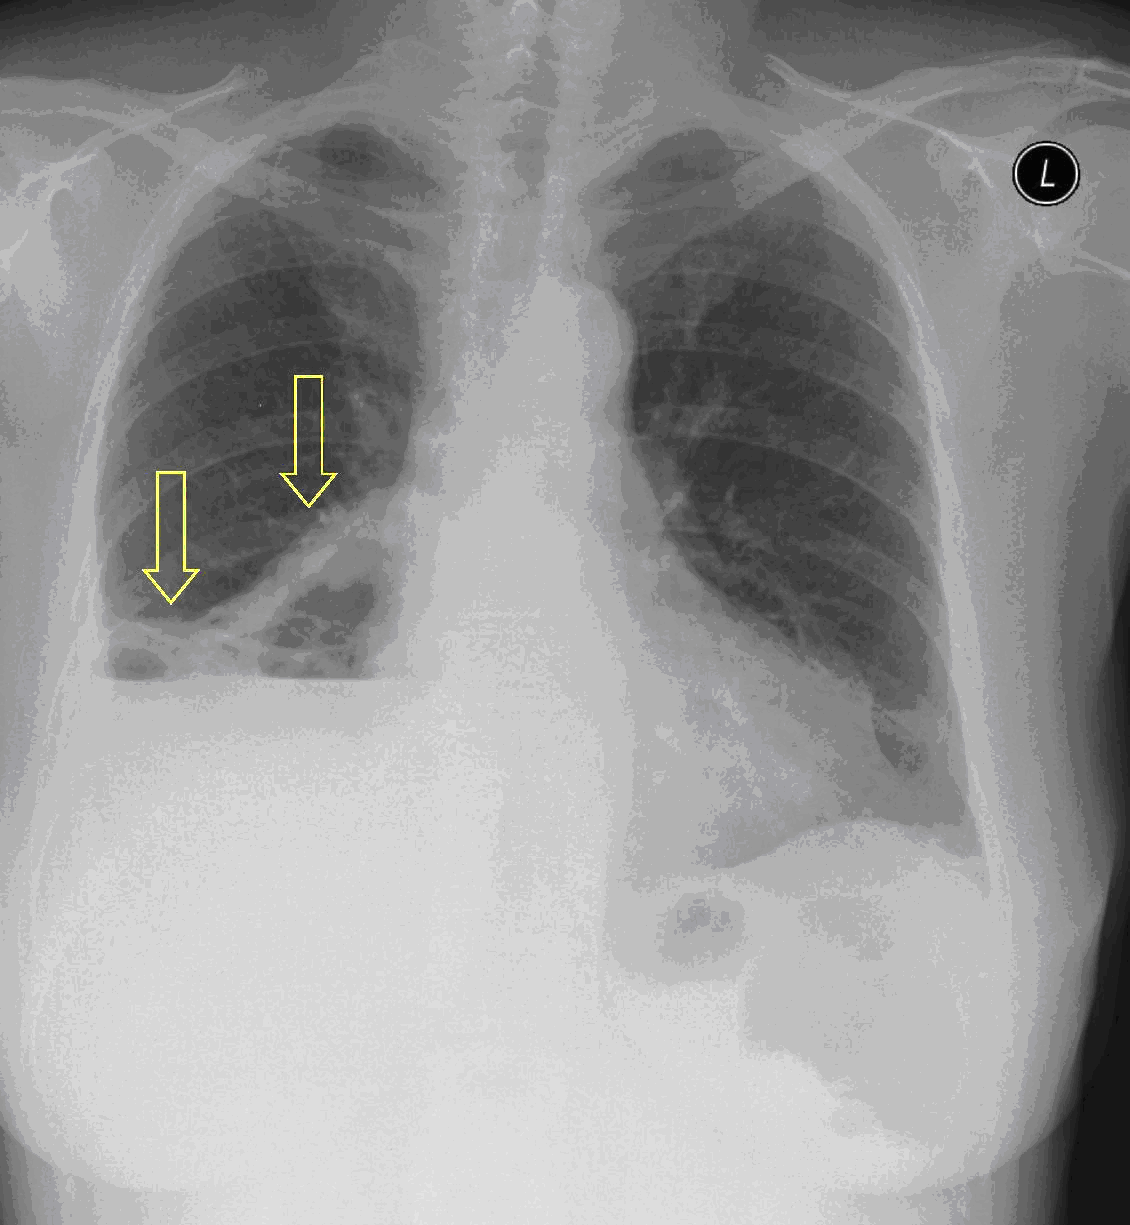

Image

2a: Atelectasis, PA chest radiograph.Hx of esophagus exstirpation surgery. (by the contribution of Zsuzsanna Monostori, MD, PhD) Parahilar right side hypolucency. (small amount of pleural effusion in the right lateral sinus)

2b. Atelectasis, left upper lobe. CECT, coronal reconstr. (by the contribution of Zsuzsanna Monostori, MD, PhD)